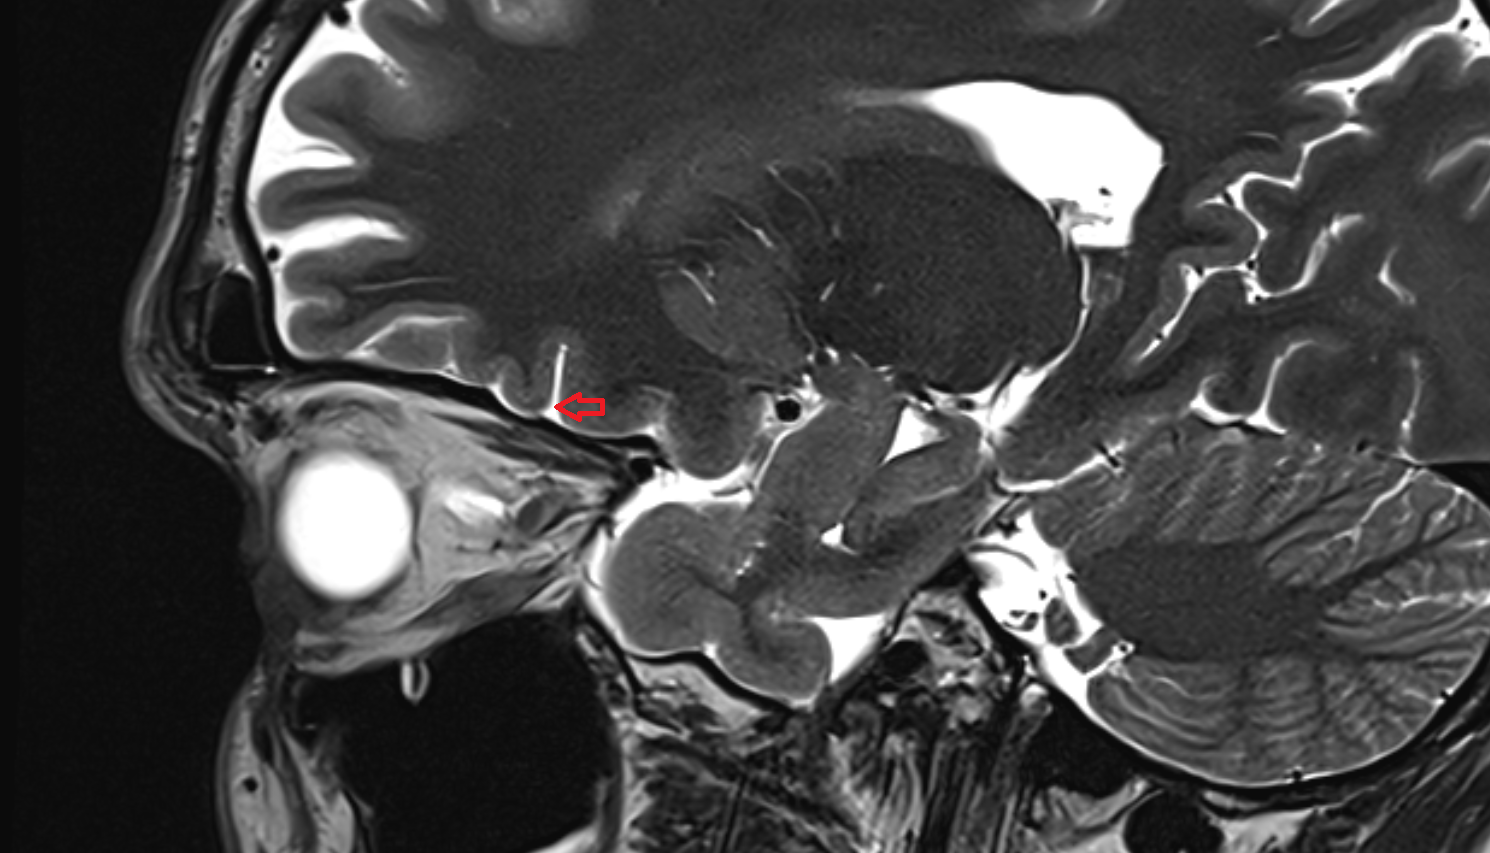

- Optic Nerve (Cranial Nerve II)

- Intracranial part of optic nerve

- Orbital part of optic nerve

- Optic nerve sheath

- Subarachnoid space of optic nerve

- Optic canal